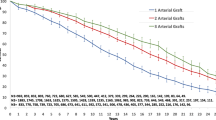

The Kaplan–Meier analysis revealed pronounced FMR progression in the C-T-BIMA group vs. L–T-BIMA + R-CABG (Fig. 2), independent of Syntax Scores (Fig. 3).

Comparison of freedom from progression of FMR in the two groups according to SS categories showed lower protection with C-T-BIMA technique in both—low–intermediate and high—SS I as well as SS II categories (Fig. 2). Thus, the L-T-BIMA + R-CABG technique performs better than C-T-BIMA in all aspects of postoperative outcome and independent of the SS scores.